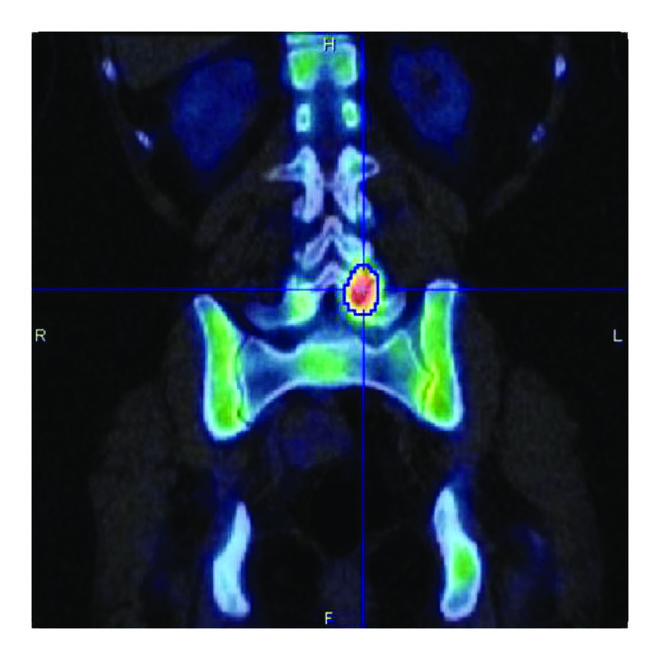

In vivo validation of SPECT/CT quantification was performed on quantitative SPECT/CT of -macroaggregated albumin (MAA) liver distribution for dosimetry assessments prior to Y-90 radioembolisation in a series of 10 patients. The recovered total activity in the SPECT field of view (abdominal region centered on the liver) was on average 8% less of the total administered activity. This underestimation can be explained by the fact that part of the administered albumins were not in the field of view of the SPECT/CT acquisition as results of extrahepatic shunts in the pelvic region and the upper part of the lungs. An example is given in Figure 3(a). An example of quantification in a bone -labeled diphosphonate SPECT/CT is given in Figure 3(b).

(a)

(b)